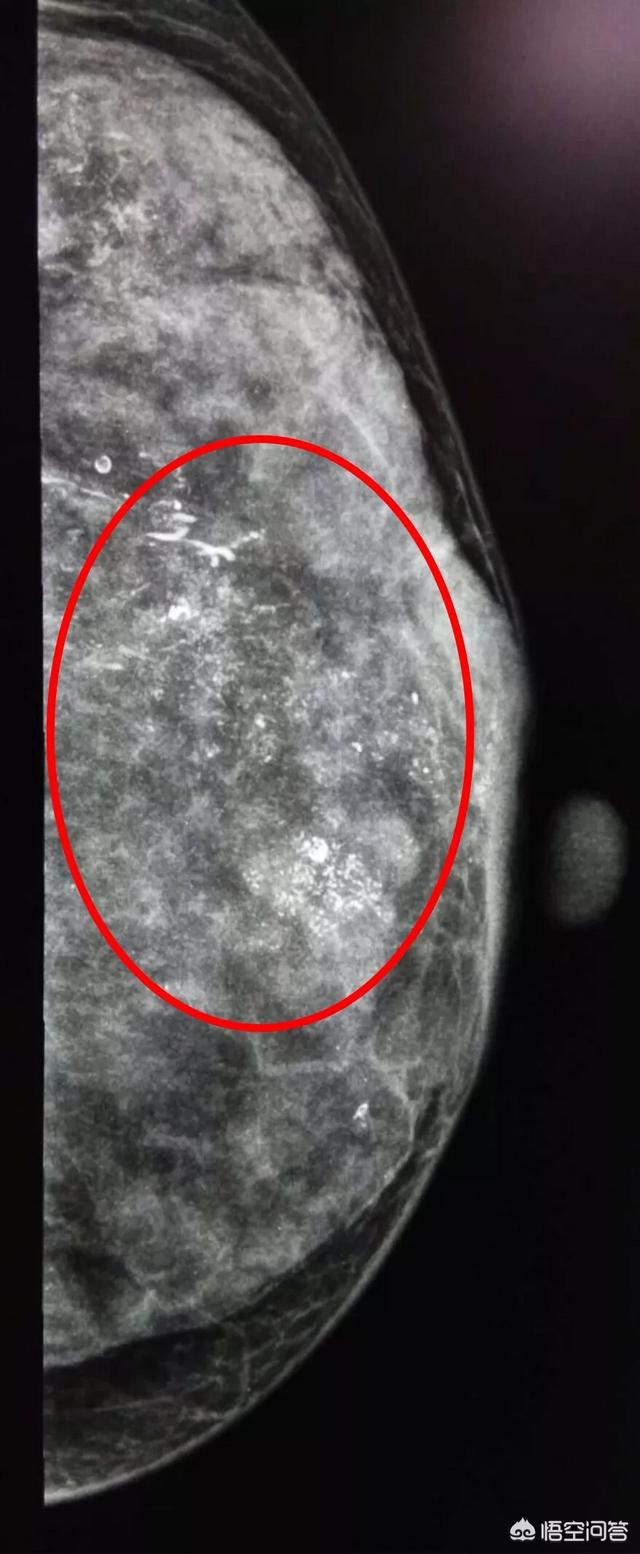

头条问答 乳腺肿块不一定是乳腺癌 可能是乳腺疾病 两者之间该如何区分 欧阳黎黎的回答 0赞

头条问答 乳腺肿块不一定是乳腺癌 可能是乳腺疾病 两者之间该如何区分 普外科曾医生的回答 0赞